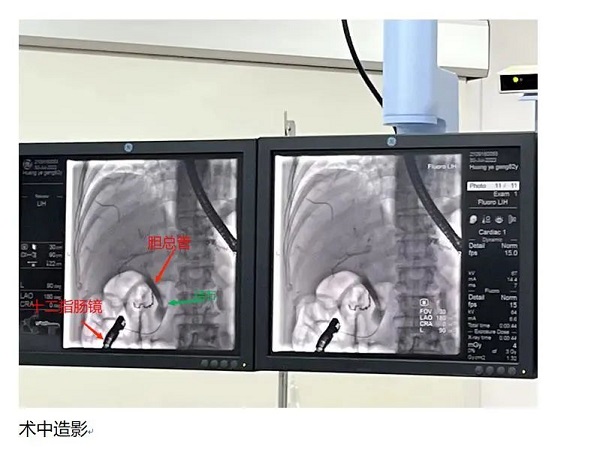

7月30日,外二科团队与介入室医生、护理和麻醉师齐心协作,成功为该患者开展了ERCP+EST术。术后患者恢复顺利,未出现并发症,目前已痊愈出院。

我院早已常规开展ERCP手术,但这位患者存在特殊情况,他曾有过“胃大部切除术(毕Ⅱ式)”史,患者的胃与十二指肠已经不直接相连,而是进行了“改道”,大部分胃已经切除,残胃与小肠吻合,需要操作十二指肠镜从“胃—空肠吻合口”进入输入袢寻找“十二指肠乳头”,这就给我们即将要进行的介入治疗带来难度。另外,我们外科人员对于万一介入失败并转而立即进行外科手术的备案提供后盾和保障。